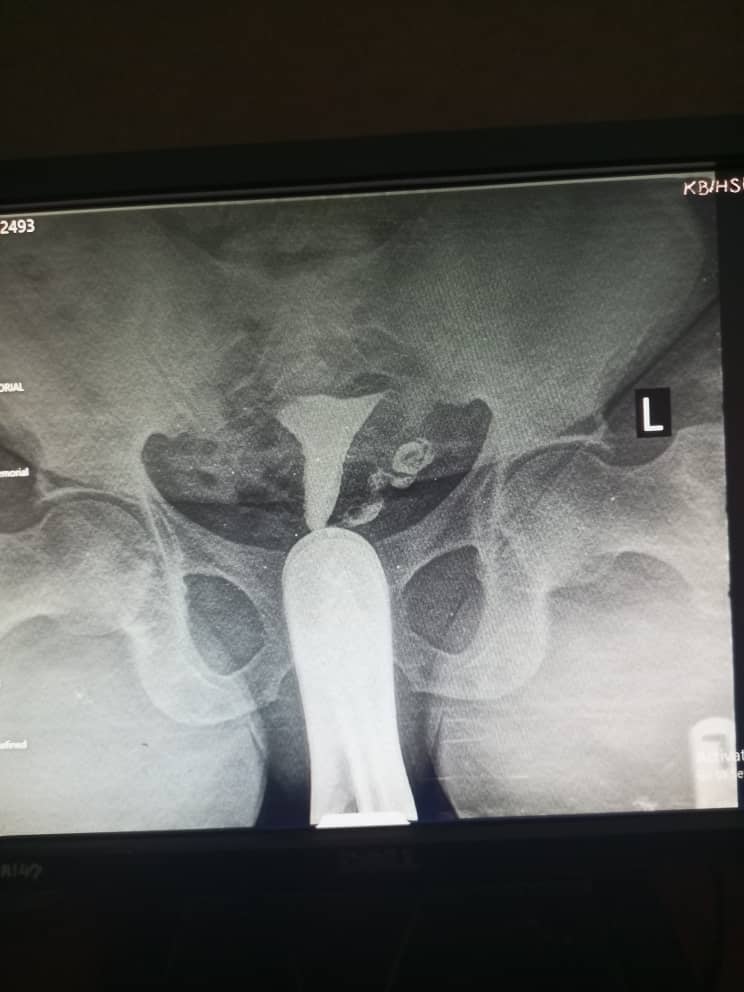

Figure 5: shows right side severe hydrosalpinx

Hydrosalpinx was seen in 28 participants (9.4%); a prevalence consistent with studies in Sokoto and Oghara; North-West and South-South Nigeria respectively. However, a markedly higher prevalence of 23.3% was reported in Ilorin; North-Central Nigeria19. The higher prevalence in Ilorin might be due to a greater burden of pelvic inflammatory diseases, which are strongly associated with hydrosalpinx.